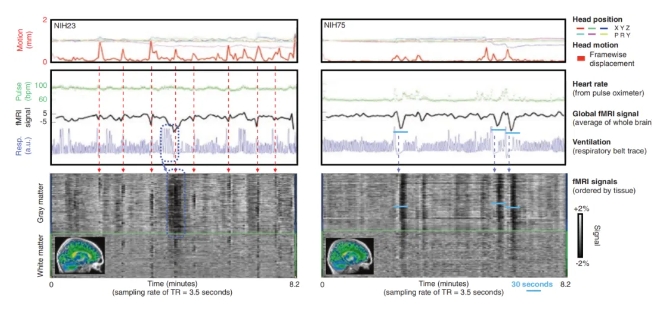

功能磁共振成像(fMRI)已被确立为在临床和科研中非侵入性研究静息和任务或刺激相关神经活动的重要工具。功能磁共振可全面测量大脑的血氧水平活跃推出神经元集群的活动状况,通过血氧水平依赖成像(BOLD),可看出大脑在视、听、言、动等活动时大脑功能变化情况。优点疗法通过采集数千张患者在安静时大脑全景功能影像,与全球多中心、大样本、高标准的影像数据库比较分析,为“解”出异常功能脑环路做好数据准备。

功能磁共振采集的信号

引自 Ulmer等,fMRI Basics and Clinical Applications,2020[2]